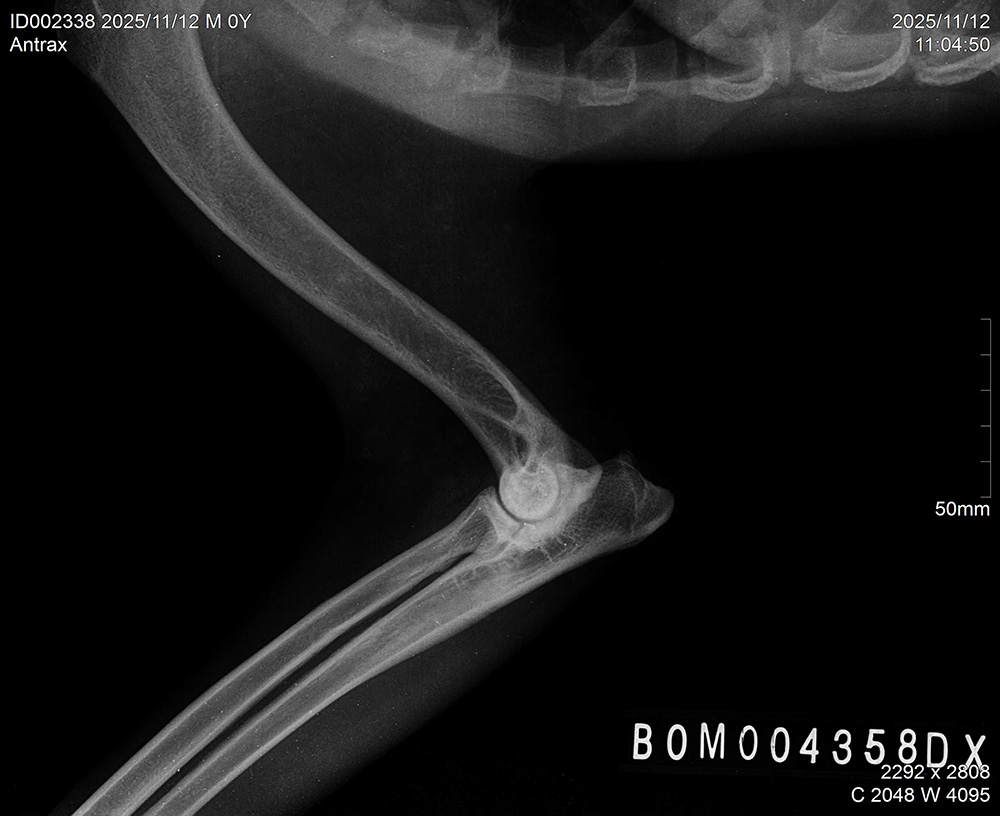

| ANTRAX, DOB July 2 2024, elbows/hips/spine: see x-rays below. ATRAX is almost 2 years old malinois male that was raised in the kennel. He is used to stay both inside the kennel as well as inside of house. He is good with other dogs and has no problem with other animals. ATRAX is a normal social dog and he gets used to the new handler and environment quickly. ANTRAX doesn't have problem with any kind of surface. ANTRAX has excellent ball drive. He is able to search for hidden ball in very hard environments and conditions. He searches with great interest and persistance until he finds the ball. His protection is also excellent. He has fast and hard bites. He is able to work inside and outside of buildings and he can bite on sleeve as well as bite suit. ANTRAX is suitable as a dog for personal protection or as a dual purpose law enforcement dog. |

X-RAYS: